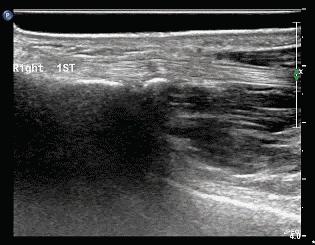

右手拇指运动,长轴切面掌指关节水平,可见拇长屈肌腱伸展时受限、停滞,A1滑车近端屈肌腱肿胀,在经历一小段时间停滞后,突然向指尖方向弹射。